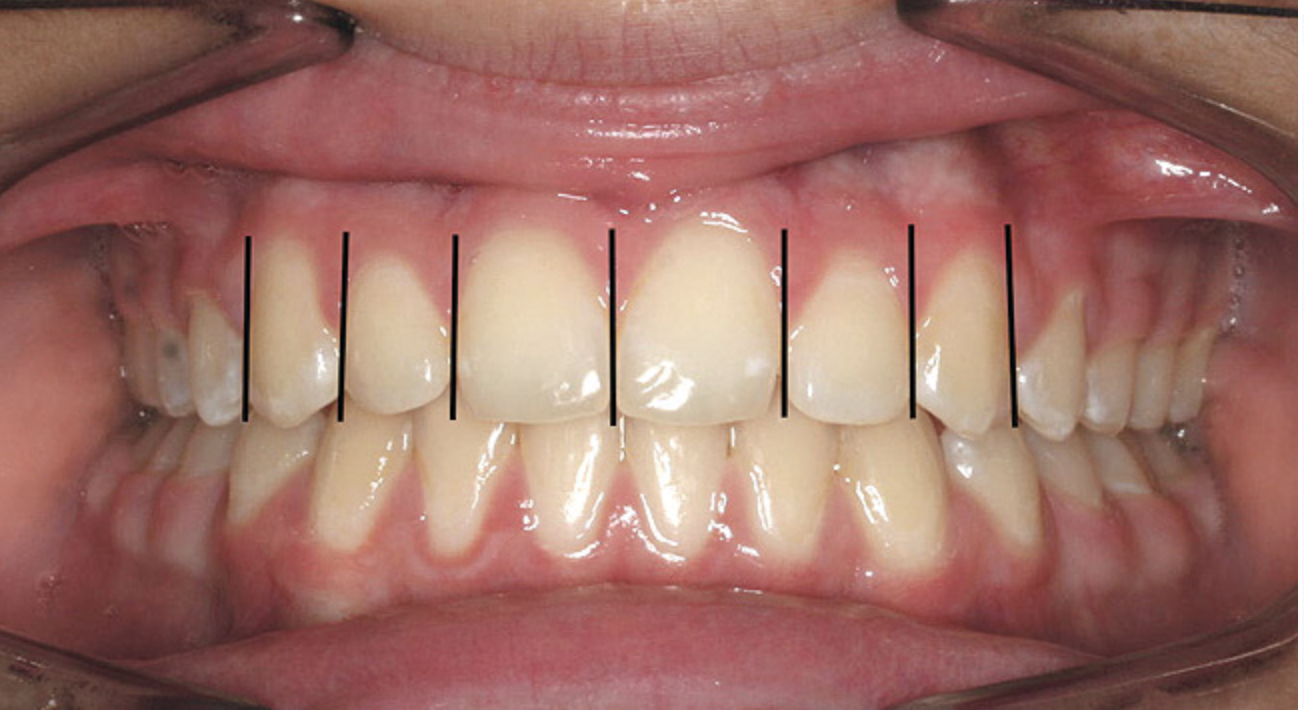

The dental midline can be improved within limits by restorative procedures. However, if orthodontic alignment is to be performed, the orthodontist plans treatment to ensure the position and vertical axis of the midline is harmonious with the facial esthetics (Figure 1).

Figure 1  Dental midlines should be as close to coincident as possible. Gingival height of maxillary lateral incisors should be even with a line between the gingival height of the central incisor and canine to 1.5 mm below that line.

Figure 1